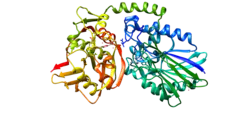

Ecto-5-prime-nucleotidase (5-prime-ribonucleotide phosphohydrolase; EC 3.1.3.5) catalyzes the conversion at neutral pH of purine 5-prime mononucleotides to nucleosides, the preferred substrate being AMP. The enzyme consists of a dimer of 2 identical 70-kD subunits bound by a glycosyl phosphatidyl inositol linkage to the external face of the plasma membrane. The enzyme is used as a marker of lymphocyte differentiation. Consequently, a deficiency of NT5 occurs in a variety of immunodeficiency diseases (e.g. see MIM 102700, MIM 300300). Other forms of 5-prime nucleotidase exist in the cytoplasm and lysosomes and can be distinguished from ecto-NT5 by their substrate affinities, requirement for divalent magnesium ion, activation by ATP, and inhibition by inorganic phosphate.[7]